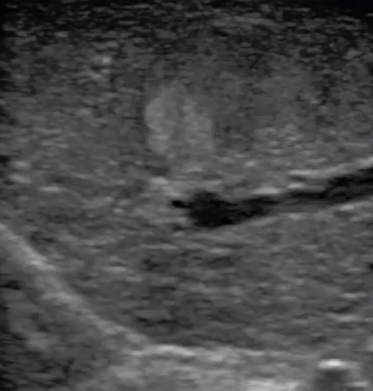

2宮腔專用探頭

多數(shù)的生殖科醫(yī)生對(duì)于受精卵的植入采用憑經(jīng)驗(yàn)操作或是使用傳統(tǒng)腔內(nèi)探頭引導(dǎo),同樣存在手術(shù)空間小、受精卵放置位置不確定等風(fēng)險(xiǎn)。專業(yè)的宮腔專用探頭,配合專用的窺器使用,為醫(yī)生提供最大的手術(shù)視野。

胎移植臨床圖